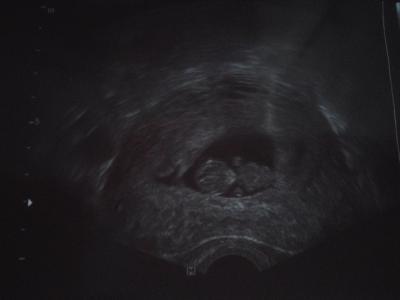

Und es sieht alles ganz super aus! Da wo vorher nur eine Fruchthülle mit einem Dottersack zu sehen war ist jetzt ein Fötus! Wir konnten das kleine Köpfchen von oben sehen, die beiden Gehirnhälften sahen schon mal gut aus. Dann hat Fr. Dr. den US gedreht und wir konnten das Ganze bestaunen. Es gibt es keine Worte dafür. Es paddelte kräftig mit seinen Arm- und Beinflossen und das Herzchen blubberte vor sich hin. Boah, da mussten wir "Eltern" aber erst mal ein Tränchen verdrücken... Mein Mann hat die ganze Zeit meine Hand gehalten und war mächtig stolz. Es gab noch ein kleines Bildchen und sie hat den ET auf den 01.04. festgelegt. Blut wurde abgenommen und nächste Woche soll ich nochmal reinkommen, dann machen sie alle anderen Untersuchungen und ich bekomme den Mutterpass! Ich könnte gerade die ganze Welt umarmen! Jetzt muss ich aber erstmal das Grinsen aus dem Gesicht bekommen und brav weiterarbeiten... LG

Bild zu ENDLICH! FA-Termin - Forum für April - Mamis

Hey, das sind ja wunderbare Nachrichten. Und was für ein süßes Foto!

Sehr süßes Bildchen. Jetzt sieht es schon wie ein richtig kleiner Mensch aus, obwohl noch so winzig. Immer wieder unvorstellbar.